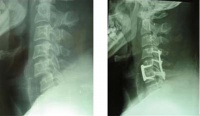

3、手术治疗

手术只能解除对脊髓的压迫和恢复脊椎的稳定性,无法使损伤的脊髓恢复功能。手术的途径和方式视骨折的类型和致压物的部位而定。

手术的指征是:

(1)脊椎骨折,脱位有关节突交锁者:

(2)脊柱骨折复位不满意,或仍有脊柱不稳定因素存在者:

(3)影像性显示有碎骨片凸出至椎管内压迫脊髓者:

(4)截瘫平面不断上升,提示椎管内有活动性出血者。 MRI显示脊髓内有出血者可在脊髓背测正中切开脊髓至中央沟,清除血块与积液,有利于水肿的消退。 手术后的效果术前年年难以预料,一般而言,手术后截瘫指数可望至少提高一级,对于完成性截瘫而言,提高一级并不能解决多少问题,对于不完全性截瘫而言,提高一级移意味着可能改善生活质量。为耍杂诓煌耆越靥闭吒Τ只取U庖辉蚋褂糜诔戮尚怨钦邸?